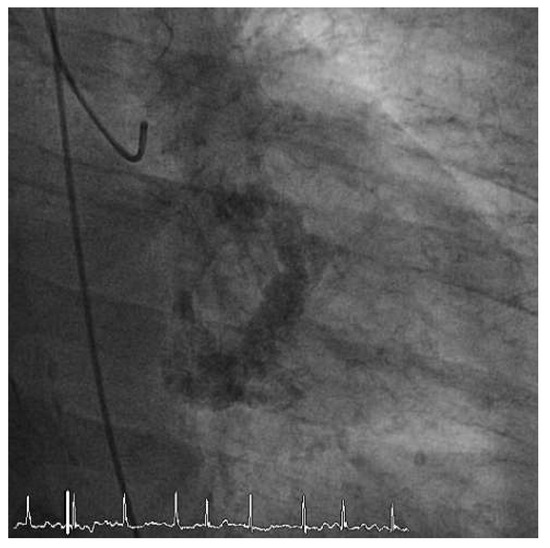

We report on the worldwide first implantation of a transcatheter valve in mitral position using a surgical approach to treat severe combined mitral valve disease, complicated by massive calcifications of the whole mitral anulus. The management of suc...